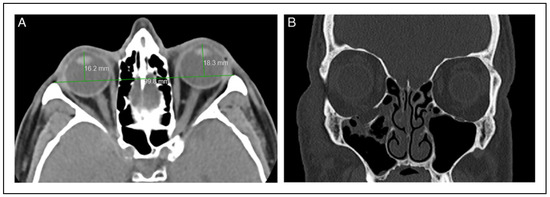

Finally, CT can be used either by measuring the difference between mirror image overlay or constructing a perpendicular along the orbital apex to a line drawn between the lateral orbital rims. Of note, one can use the posterior surface of the cornea as a stopping point when the anterior surface is difficult to define (Figure 5A,B). This analysis is quick and easy, especially initially in patients who likely already have a CT facial protocol in the context of facial trauma. CTappears to be the most reliable technique for assessment of enophthalmos based on interobserver variation data [5]. However, enophthalmos often develops later, after pneumo-orbital, swelling from edema and a possible hematoma have subsided. Even patients with a significant orbital floor fracture generally initially present with proptosis. Obtaining a repeat or serial CT may not be practical or preferrable over exophthalmetric measurements for the patient given additional unnecessary costs and radiation exposure.

As another example, the patient in Figure 5A,B is a 71-year-old male who suffered a right orbital floor blow-out fracture after a skiing accident. He developed late enophthalmos of >2 mm by CT exophthalmometry and 3–4 mm by Naugle measurement. He is an avid ski instructor and chose non-operative management after a long discussion, because of fears of possibly developing diplopia. His enophthalmos was evident to his wife, but not the casual observer. His only complaint was with his fitting of hard contact lenses on his enophthalmic side. This visual problem was subsequently addressed with a correctional lens when he had cataract surgery.

Figure 5. (A) CT exophthalmometry. A horizontal line is first made connecting the lateral orbital rims, and perpendicular lines extend to the posterior corneal surfaces. (B) Coronal CT demonstrating right orbital floor fracture which resulted in enophthalmos.